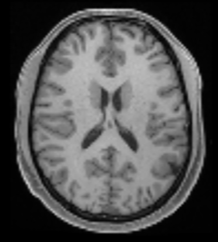

TABLE VII: Clinical evaluation for MS case

Real 3T MRI Real 7T MRI 7T-like SR MRI (3T to 7T)

In another case involving a patient with multiple sclerosis (MS), characterized by periventricular and subcortical white matter abnormalities. MS lesions, often appearing as small “dark holes” in the brain on T1w MRI, are notoriously difficult to identify on lower-field MRIs. As shown in Table VII, the real 7T MRI provided a significant improvement in resolution compared to the 3T MRI, enabling clearer visualization of MS-related changes in the periventricular regions, which highlights the importance of 7T MRI in detecting subtle lesions. By applying our student model to super-resolve the 3T MRI into a 7T-like quality, the resulting SR image closely matched the real 7T MRI, markedly improving the depiction of the periventricular white matter, making the small “dark holes” indicative of MS lesions much more apparent.